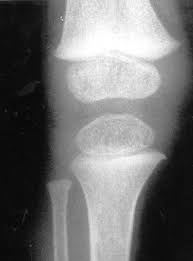

La confirmación del diagnóstico se realiza determinando la cantidad de cistina en los leucocitos (células blancas de la sangre). Es frecuente observar la presencia de cristales de cistina en la córnea.